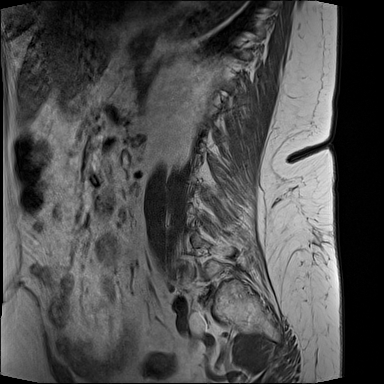

19.01.2024

MRT Lendenwirbelsäule (LWS)

71 Bilder | 1024x1024 px | 15 MB

Januar 2024

MRT LWS + Röntgen Becken

MRT der Lendenwirbelsäule und Röntgen des Beckens zur Diagnostik

MRT LWS (Lendenwirbelsäule)

DICOM

MRT mit 71 Bildern